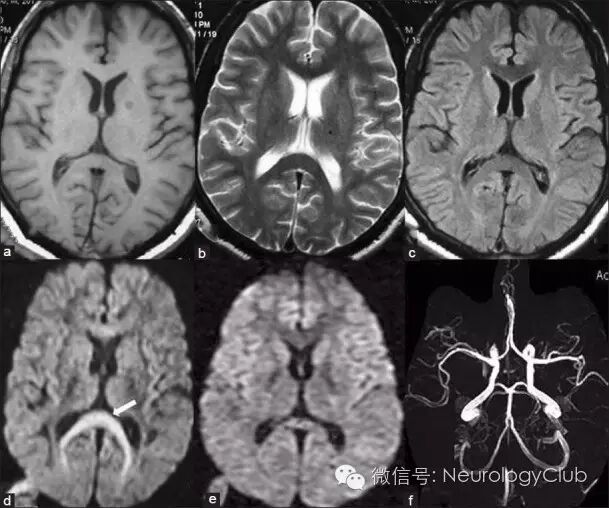

(图4:激素治疗相关的RESLES。A:T2WI;B:FLAIR;C:DWI;D:ADC;3周后病灶消失

(图5:癫痫发作相关的RESLES。a:T1WI;b:T2WI;c:FLAIR;a-c未见SCC异常信号;d:DWI可见“回旋镖征”;e:DWI,6月后复查病灶消失;f:MRA无殊

磁共振是诊断RESLES的首选检查。其特征性的影像学表现为SCC(一般位于中心区域)局限性的椭圆形或条状的病变,如出现整个胼胝体压部受累的条状病变,称为“回旋镖征”(Boomerang sign)。病灶于T1WI上呈等或低信号,T2WI/FLAIR和DWI上均为高信号,ADC值降低,增强扫描无明显强化。目前尚无胼胝体压部发生囊病或坏死的报道。病变可不仅仅局限在胼胝体压部,其他部位如膝部、体部也可同时出现,甚至可以累及胼胝体外,如脑室旁白质,皮质下白质和基底节区,而这些病灶基本上也是可逆的。最近的研究表明,胼胝体外病变的出现往往提示预后不良,而胼胝体其他部位是否出现病灶与预后并无明显联系。各种病因导致的RESLES影像学异常和消失的时间如表1所示。